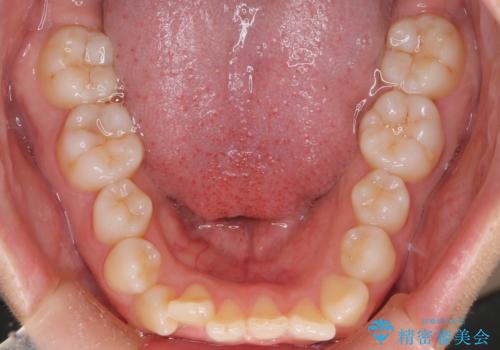

- 「前歯が出ているのが気になる」との主訴で来院されました。診察の結果、上下の前歯が前方に突出し、口元がやや目立つ印象でした。また、歯列の中心線(正中)も上下でずれており、かみ合わせのバランスにも問題がありました。

治療はまず精密スキャンとシミュレーションを行い、TADを使用して奥歯を遠心移動(後方へスライド)させる設計を組み込みました。マウスピースは計画に沿って順次交換し、TADと連結しながらコントロールすることで、歯列全体を無理なく整えていきました。

前歯の傾きが改善され、横顔の印象が大きく変化。上下の正中も一致し、かみ合わせのバランス(臼歯関係)も整いました。目立たず快適に治療ができた点にもご満足いただき、「人に気づかれずにここまで変化できるとは思わなかった」とのお声をいただいています。治療後はリテーナーを用いて、仕上がりをしっかり保っています。